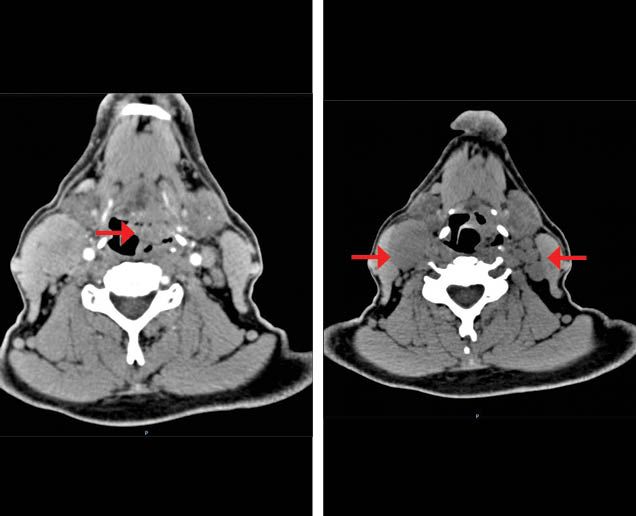

The nasofibrolaryngoscopy described a tumor at the hypopharynx that invaded the epiglottis and the posterior pharyngeal wall, with fixation of the right hemilarynx. An endoscopy ruled out extension to the esophagus. The CT scan described the presence of a tumor at the hypopharyngeal level with transglottic extension. It also revealed bilateral cervical matted lymph nodes (Figure 1a). Chest CT scan ruled out distant metastases; the complete blood count and blood chemistry were normal. The patient was given a diagnosis of a stage IVB (T3N3M0) hypopharynx SCC.

Figure 1A. Basal contrast enhanced CT scan shows a tumor with heterogeneous enhancement located in the pharyngomucosal space (hypopharynx) with lost interface with the lateral portion of the glottis (left). Right cervical matted nodes in level IIA and multiple left cervical nodes (right).